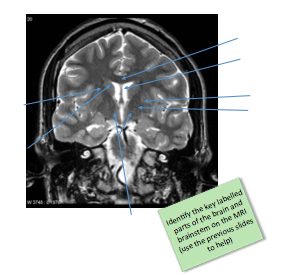

Label the image shown

What is the thalamus composed of?

Label the image

How does neural tissue appear on a T2 MRI after a stroke?

What is a watershed infarct?